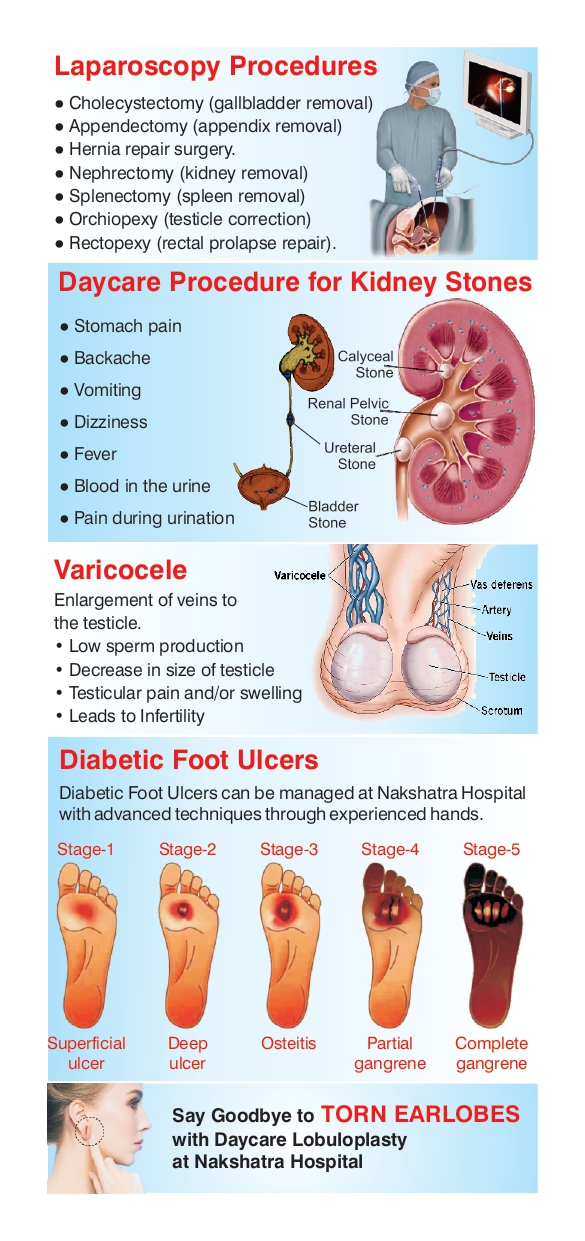

Varicocele

A varicocele (VAR-ih-koe-seel) is an enlargement of the veins within the loose bag of skin that holds the testicles (scrotum). These veins transport oxygen-depleted blood from the testicles. A varicocele occurs when blood pools in the veins rather than circulating efficiently out of the scrotum

diabetic foot ulcer

A diabetic foot ulcer is an open sore or wound that occurs in approximately 15 percent of patients with diabetes, and is commonly located on the bottom of the foot. Of those who develop a foot ulcer, six percent will be hospitalized due to infection or other ulcer-related complication.

Surgeries We Offer

Appendicitis

Gall Bladder Stones

Umblical Hernia

Inguinal Hernia

Epigastric Hernia

Incisional Hernia

Varicose Veins

Hydrocele

Kidney Stones

Diabetic Foot Management

Ear Lobe Repair